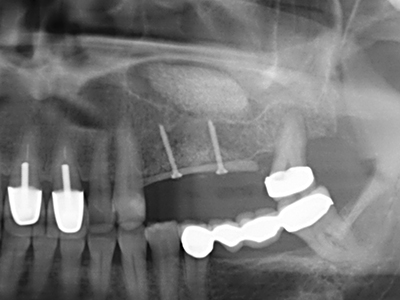

Die Präparation des lateralen Fensters bei der externen Sinusbodenelevation stellt gerade für chirurgisch unerfahrene Implantologen eine große Herausforderung dar. Die knöcherne Bedeckung der Kieferhöhle ohne eine Verletzung der darunterliegenden Schneider’schen Membran abzutragen ist dabei nur ein Teil der Operation – nach Schaffung eines ausreichenden Zugangs muss die Kieferhöhlenschleimhaut vorsichtig mobilisiert werden, um Raum für das einzubringende Material bzw. die Implantate zu schaffen. In dieser Indikation ist die Piezochirurgie zweierlei hilfreich: zum einen kann durch Verwendung diamantierter Instrumente eine selektive Knochenabtragung erfolgen und die darunter liegende Schleimhaut bleibt bei vorsichtiger Vorgehensweise intakt. Zum anderen unterstützen die Ultraschallfrequenzen zusätzlich eine komplikationslose Ablösung der Schleimhaut – sie werden durch spezielle stumpfe Ansätze in den Spaltraum zwischen Schleimhaut und Kieferhöhlenboden übertragen (Cassetta, Ricci et al. 2012, Pereira, Gealh et al. 2014) (Rickert, Vissink et al. 2013). So erscheint es nicht verwunderlich, dass in aktuellen Übersichtsarbeiten über die externe Sinusbodenelevation neben der Verwendung von rauen Implantatoberflächen und dem Einsatz von Knochenersatzmaterialien auch der Einsatz von piezoelektronischen Geräten als positiv bewertet wird (Wallace, Tarnow et al. 2012).

Bei der Knochenblockentnahme zeigen sich weitere Vorteile für die Piezochirurgie: Neben der bereits beschriebenen hohen Präzision bei der Osteotomie stellt sich gerade die Verwendung der dünnen Sägespitzen als besonders materialschonend heraus. Bei der Verwendung insbesondere von Lindemannfräsen sind mit deutlich höheren Entnahmeverlusten durch die dickere Instrumentenspitze zu rechnen (Lakshmiganthan, Gokulanathan et al. 2012). Die insbesondere bei retromolar entnommenen Blocktransplantaten notwendige basale Abtrennung wird durch speziell hierfür vorgesehene rechtwinklige Sägen erleichtert, so dass die Piezochirurgie als präzises, übersichtliches und sicheres Verfahren zur retromolaren Knochenblockgewinnung angesehen wird (Happe 2007) (Abb. 1-12).